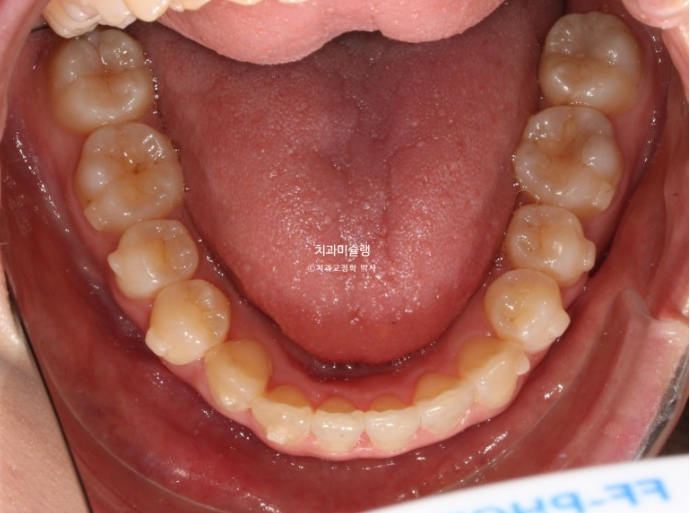

오늘은 비발치 교정 사랑니 공간을 이용하여 덧니와 중심선, 가위교합을 개선한 증례를 보여드리겠습니다.

덧니가 보이고 파란화살표에 소구치에 가위교합도 있습니다.

발치가 필요할 정도의 덧니나 돌출입은 아니여서 비발치로 매복된 사랑니를 빼고 사랑니 공간을 이용하여 어금니를 뒤로 이동 시키는 치료를 권유드렸습니다.